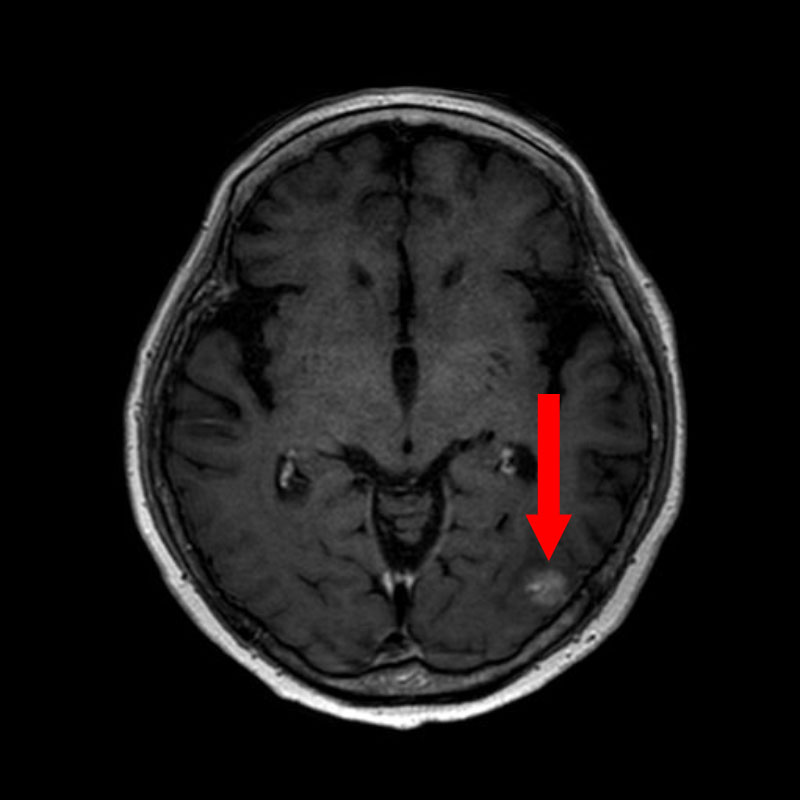

No.’25_25 手術前1

No.’25_25 手術前2